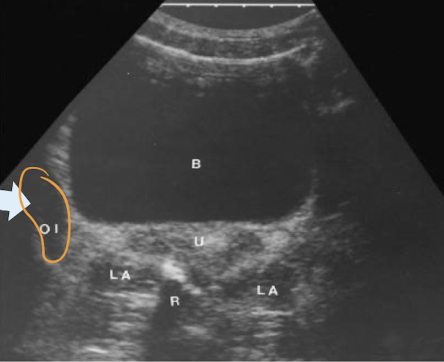

SONO: vagina, cervix, uterus

TA pelvic anatomy in TRANS

starting TRV is easiest way to find ovaries